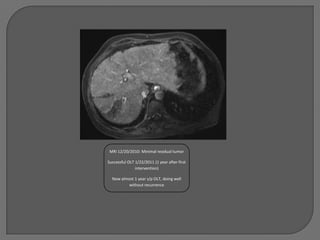

MRI 12/20/2010: Minimal residual tumor

Successful OLT 1/22/2011 (1 year after first

intervention)

Now almost 1 year s/p OLT, doing well

without recurrence